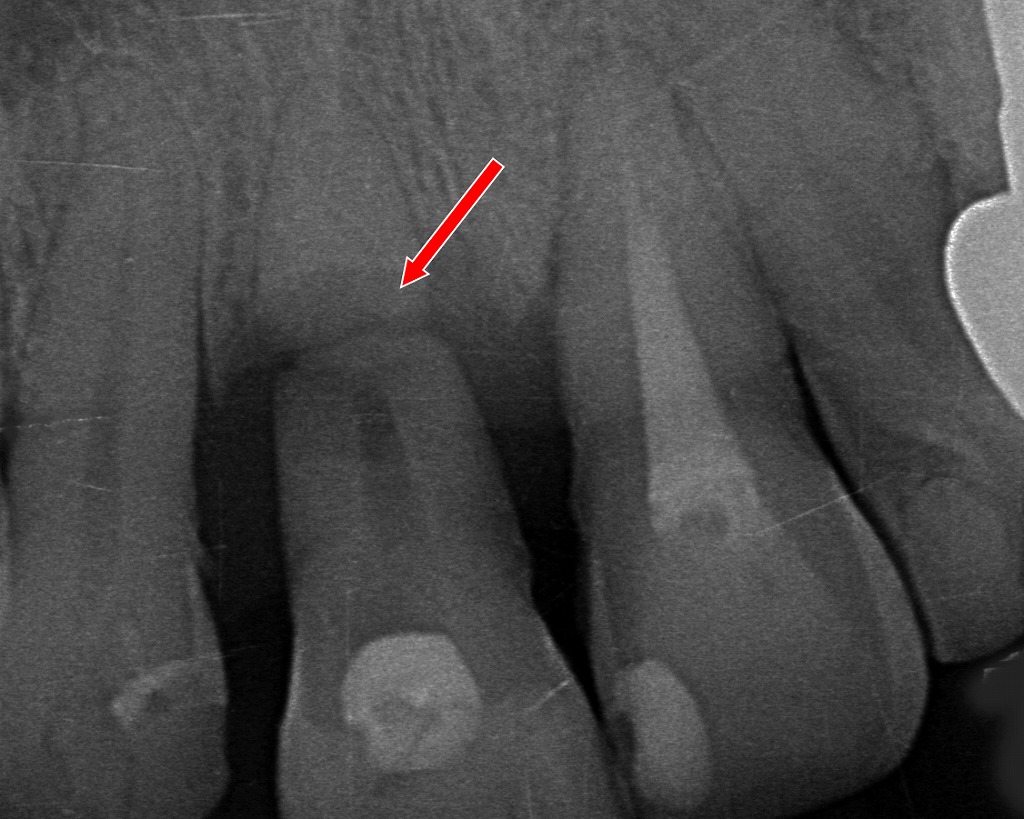

歯根まで折れた場合

歯の根っこまで破折している場合は、残念ながら抜歯が必要になることも。その場合はブリッジ・入れ歯・インプラントといった選択肢から治療法を選びます。特にインプラントは機能性・審美性の両面で優れています💡。

赤矢印が示す部分では、歯の根(歯根)が折れており、この状態は修復や根管治療では保存が不可能です。歯根破折は進行性で、細菌感染が広がるため、このケースの場合“抜歯が唯一の適切な治療”となります。